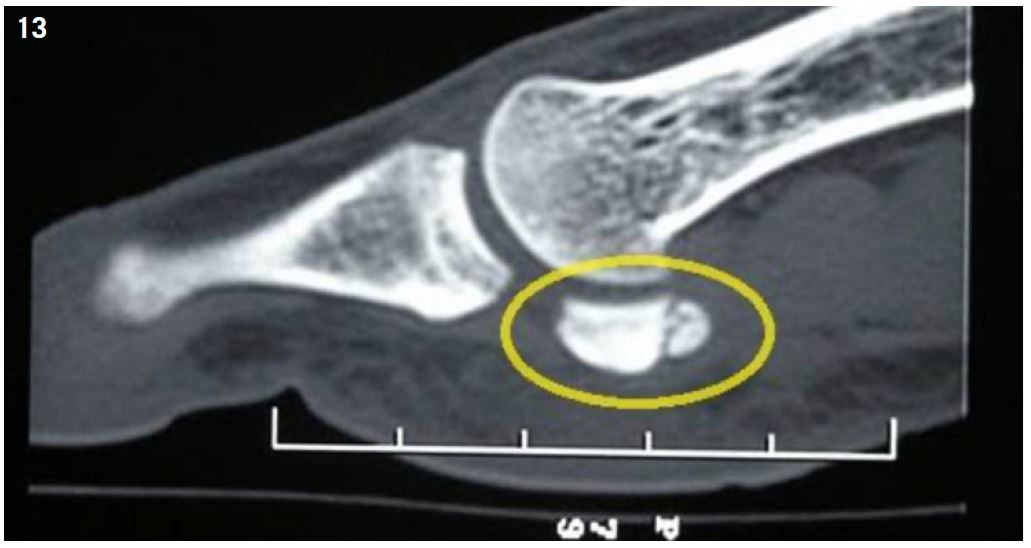

The diagnosis is generally made with an MRI or a CT scan31 (Figure 13).

Treatment is medical, involving 6 to 8 weeks of non-weight bearing, followed using orthotics. Surgical treatment is the last option (after carrying out a local anesthetic test). It is generally a hemi-sesamoidectomy or a sesamoidectomy. Some authors propose a temporary arthrodesis by double pinning for a period of six to eight weeks. Return to a sport activity after a hemi-sesamoidetomy can be expected after three months5.

Figure 13: Sesamoid bone stress fracture (CT SCan).